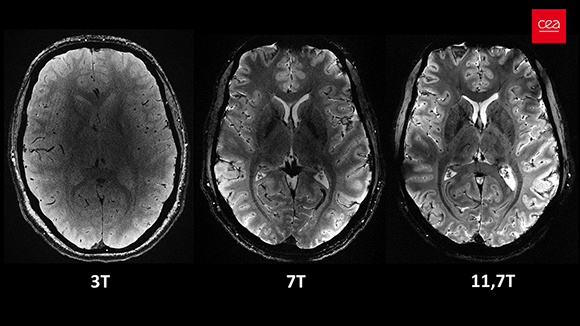

قادر على المسح بدقة 0.2 مم، وإكمال مسح جميع أقسام الدّماغ في أربع دقائق فقط. دماغ في MRI بقوة 11.7 تسلا (يمين) مقارنة بأجهزة أضعف | © CEA

تستمرّ الأدوات التي تخدم دراسات الدماغ الحيّ في التّحسّن، من بين ذلك استخدام أجهزة MRI أكثر قوّة، والّتي توفّر مسوحات تشريحيّة مفصّلة للغاية. الجهاز الأقوى اليوم موجود في فرنسا وتصل قوّته إلى 11.7 تسلا. وهو قادر على المسح بدقّة 0.2 مم، وإكمال مسح جميع شرائح الدّماغ في أربع دقائق فقط. للمقارنة، تستخدم معظم المستشفيات في إسرائيل أجهزة MRI بقوّة 1.5 تسلا، وهي كافية لمعظم الاحتياجات الطّبّيّة. في دراسات الدّماغ، من المعتاد استخدام جهاز بقوة 3 تسلا، وفي معهد وايزمان للعلوم يوجد جهاز يصل إلى 7 تسلا.